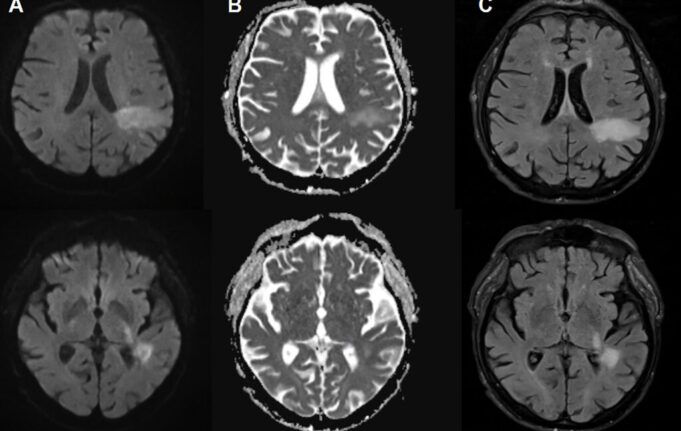

Nella PML, il nuovo virus patogeno, o virus JC “tipo PML”, attacca attivamente il cervello, distruggendo specifiche cellule cerebrali, tra cui cellule Forma la guaina mielinica isolante che protegge le cellule nervose. Ciò porta a un’estesa demielinizzazione, che porta alla disfunzione e alla morte delle cellule nervose. All’imaging, la PML può presentarsi come una lesione caratteristica nel cervello. Queste lesioni illustrate, insieme ai risultati dei test per il DNA del virus JC nel liquido cerebrospinale, rappresentano il modo in cui viene diagnosticata la PML. Ma per i pazienti affetti da leucemia promielocitica, i sintomi possono simulare qualsiasi cosa, dall’ictus alla sclerosi multipla, causando impedimenti nel linguaggio, difetti visivi, disfunzione motoria e convulsioni.